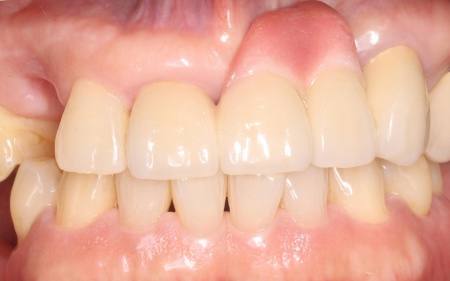

十分な治癒を確認したうえでお口全体の型取りを行い、技工所で入れ歯を作製しました。

後日、完成した入れ歯を患者様のお口に合わせて細かく調整し、装着時の違和感や噛み合わせに問題がないかを丁寧に確認して、治療を終了しました。